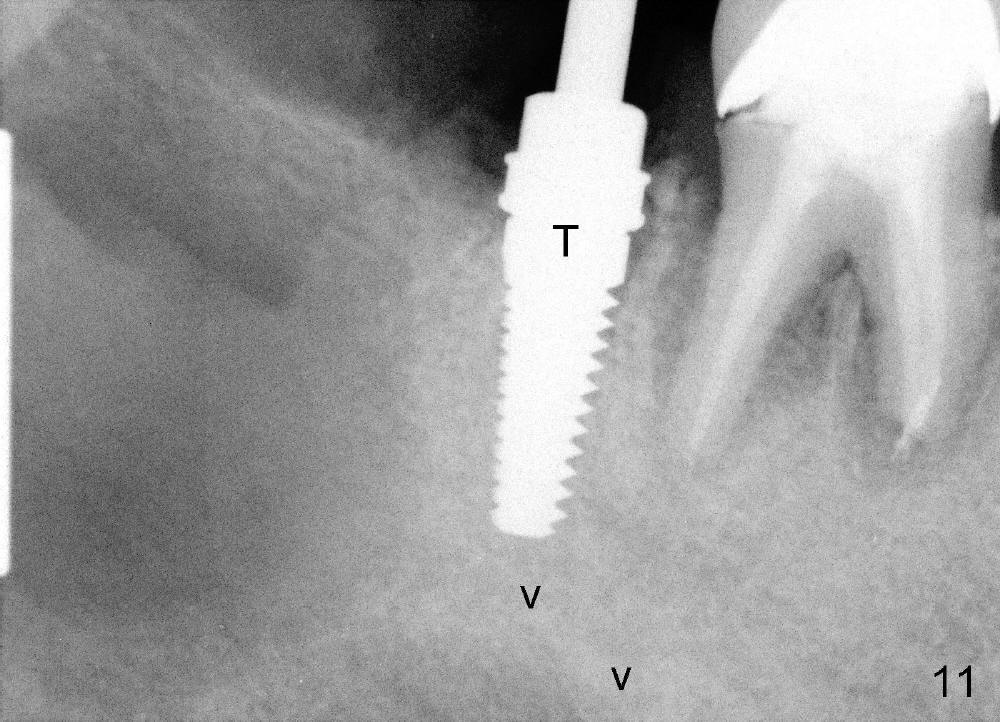

osteotomy is created in the mesial socket of #31 (4.5x17 mm tap in place: T

(Fig.10,11)). A 5x17 mm implant is placed with high torque (Fig.12 I).